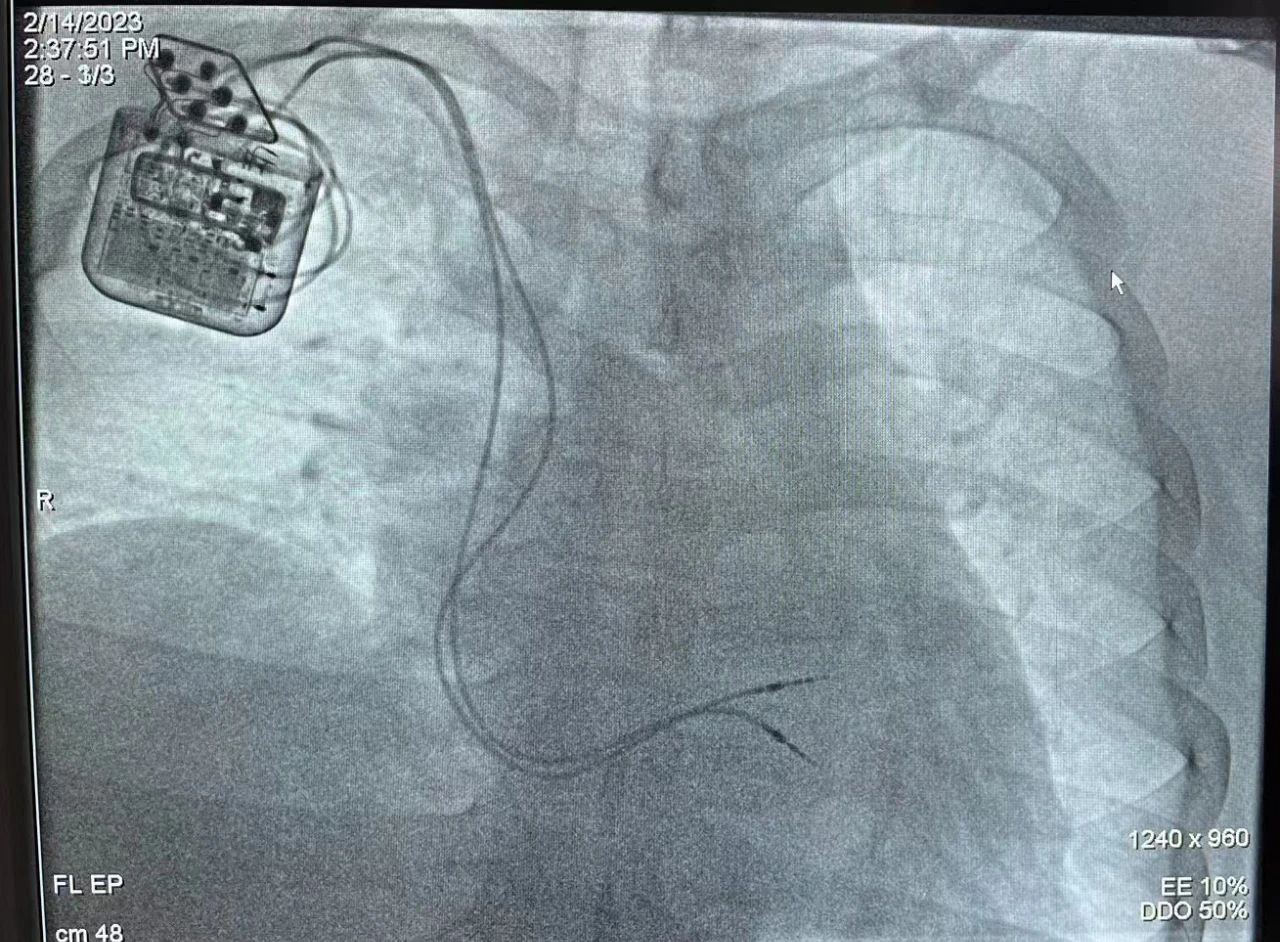

2月14日,在医院和相关职能部门的支持下,心内一科主任谢瑞芹教授带领起搏与电生理团队,成功为一位严重心力衰竭、患扩张型心肌病多年的年轻患者植入心脏收缩力调节器(CCM),患者恢复良好,心衰症状明显好转,已顺...